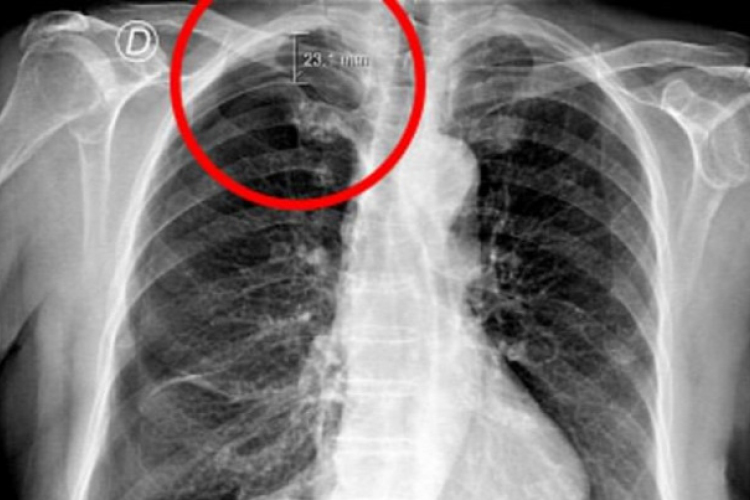

Krónikus hátfájdalma miatt fordult a 79 éves portugál asszony az ősi kínai módszerhez. Arra azonban nem számított, hogy az ártalmatlannak tűnő akupunktúrás kezelés milyen életveszélyes állapotot fog előidézni nála.